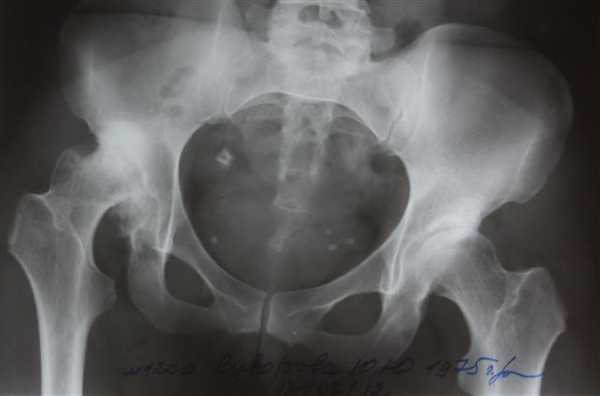

Рентгенограммы больной Т., 10 месяцев. Диагноз: врожденный вывих бедра справа.